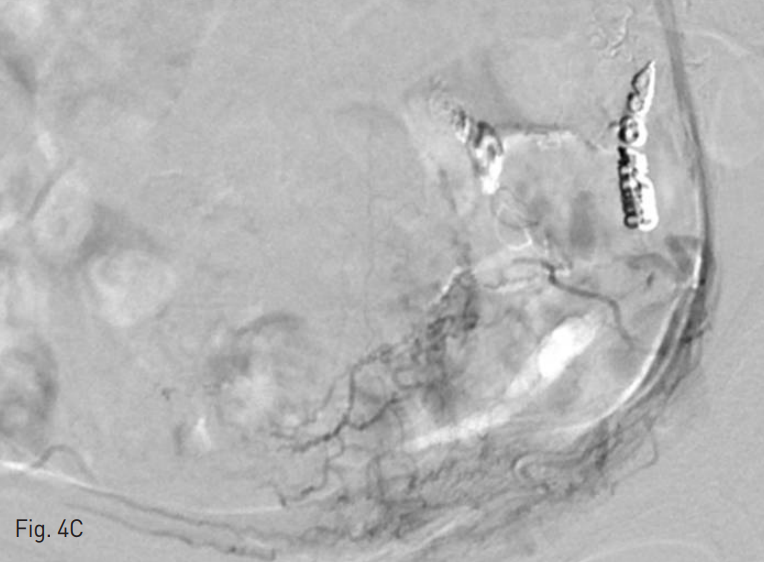

Fig. 4

Selective angiography demonstrates the uterine arteriovenous malformation fed by both uterine arteries (A~B) and multiple fine branches from left vesical artery (C) and left obturator artery (D).